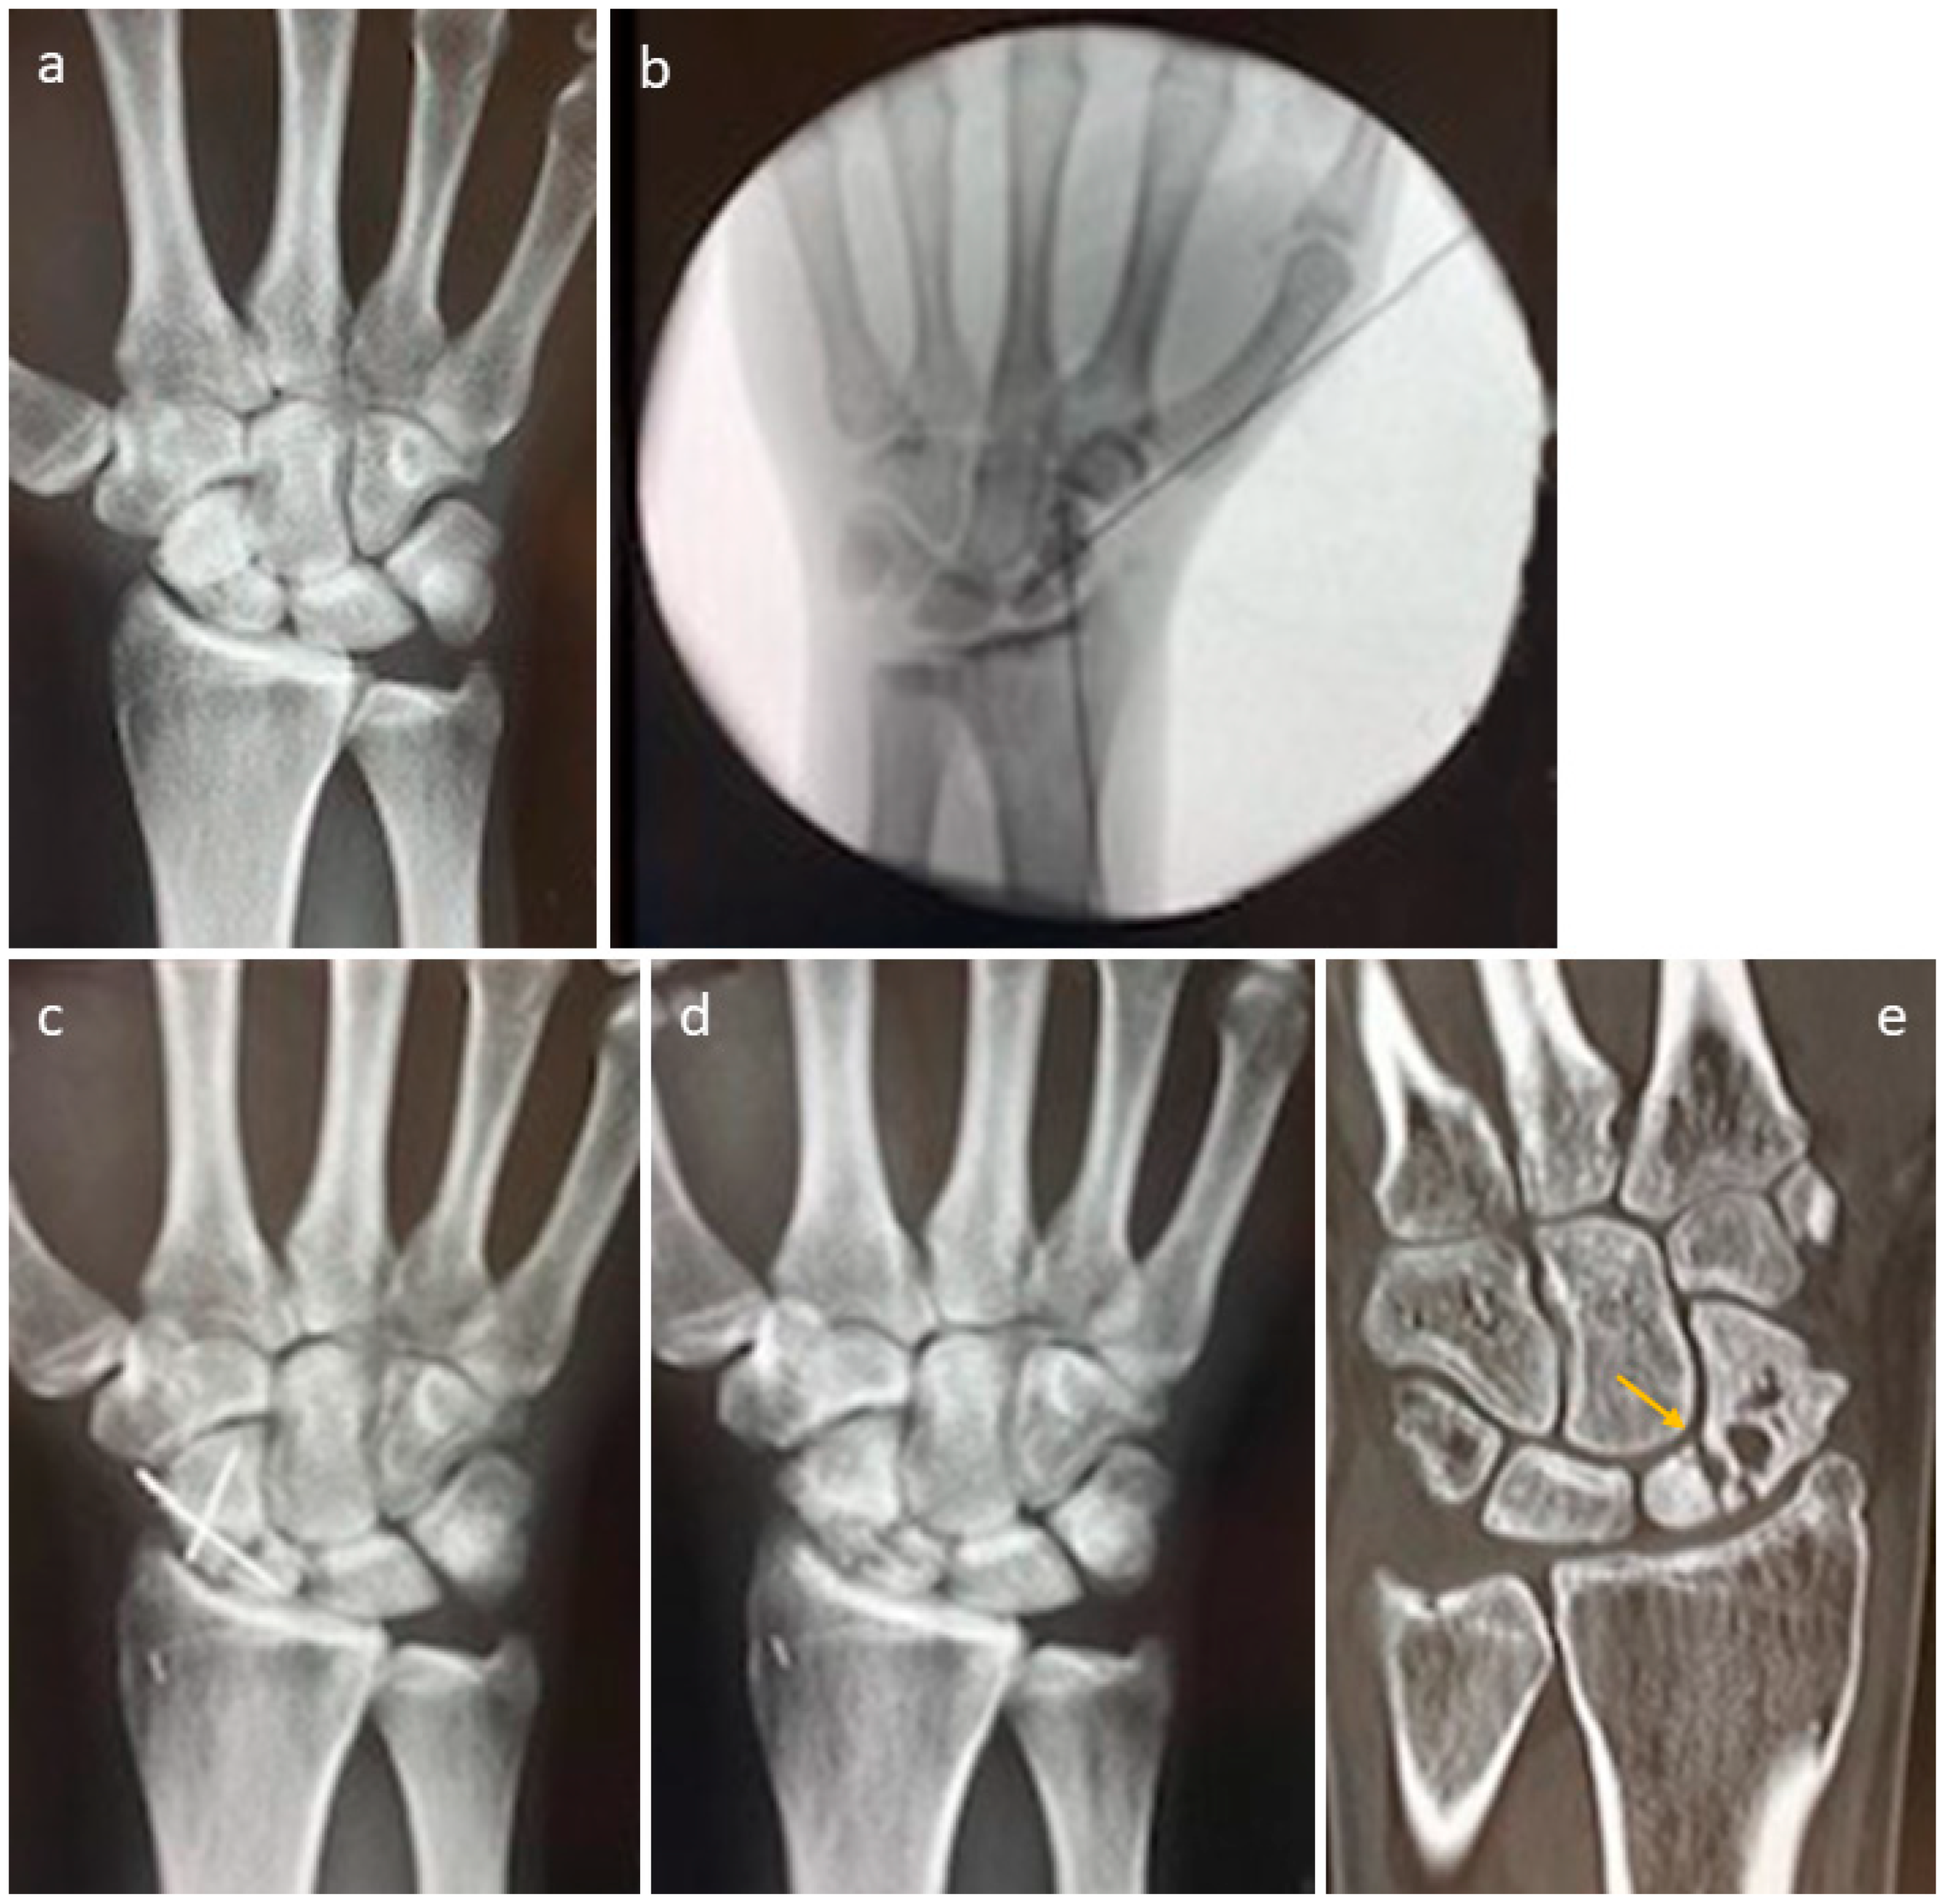

3.4. Selected Case Descriptions